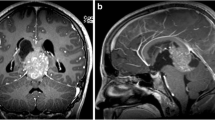

Illustrative magnetic resonance imaging based topographic anatomical tumor behavior: A—glioblastoma: example of a patient with glioblastoma of the left superior frontal gyrus. Despite the extended character of the tumor, a segmental topographic-anatomical behavior with displacement of the adjacent gyri and a tail-like relationship to the wall of the frontal horn is observed. B—Glioblastoma: another case of a patient with glioblastoma of the left occipital pole and superior occipital gyrus. Despite the extended character of the tumor, the spatial character along the ventriculo-cortical radial unit is preserved. C—WHO grade II astrocytoma: example of a patient with grade II astrocytoma of the left medial frontal gyrus. The segmental topographic-anatomical behavior of the tumor with tail-like relationship to the wall of the left frontal horn becomes evident here as well. D—Primary CNS lymphoma: this example of a patient with primary CNS lymphoma illustrates the topographic-anatomical pattern of these tumors along the projection and commissural white matter fibers. The tumor can be followed from the internal capsule, through the cerebral peduncles via the pons to the ventral medulla oblongata and the cerebellar peduncles. In addition, an infiltration along the corpus callosum can be seen. E—Primary CNS lymphoma: another example of a patient with primary CNS lymphoma, which demonstrates the tumor distribution along the short association fibers. F—Multiple metastases: a patient with multiple intracranial metastases due to an adenocarcinoma of the lung. This example illustrates both the cortico-subcortical character and the topographic-anatomical preference for watershed areas of metastases. CNS central nervous system